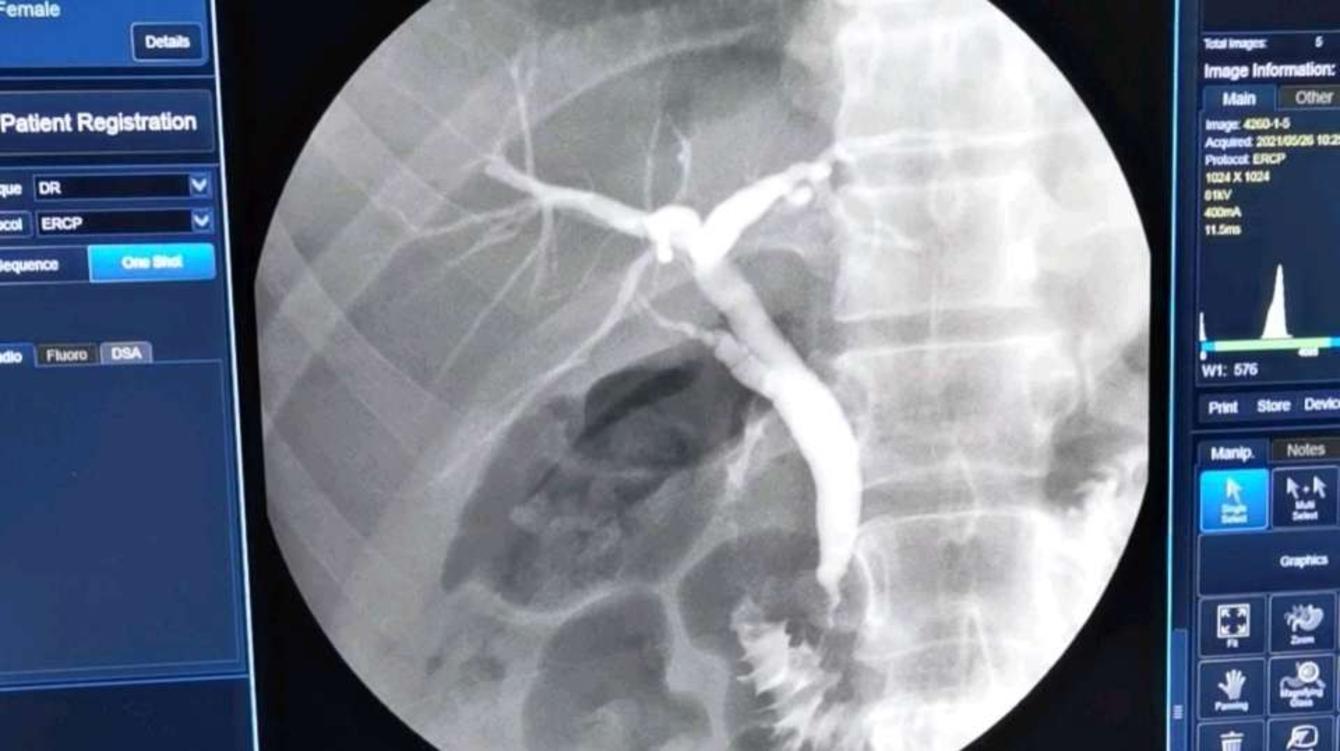

(4)十二指肠镜检查可以明确十二指肠乳头及憩室等,同时ERCP可以进一步检查明确胆胰管合流异常及胆胰管狭窄情况。

当然了,胆胰管汇合部疾病方面这些问题过于专业,科普一下就是让大家了解一下胆囊外的因素在胆石病中发生发展中的重要性,让大家了解一下为什么做了胆石病手术以后还要复发,还会有“胆囊结石胆囊炎”症状的根源所在,如果想要更多了解这方面的知识可以在各大医学网站查询我在这方面的述评、专家论坛、论著等学术论文。十二指肠镜检查ERCP了解胆道情况在行ERCP检查胆胰管汇合部疾病全国学术会议演讲关于胆胰管汇合部疾病胆胰管汇合部疾病的学术交流